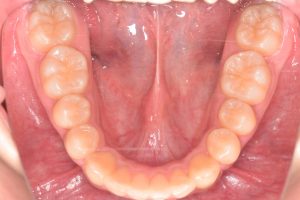

下から

下あご